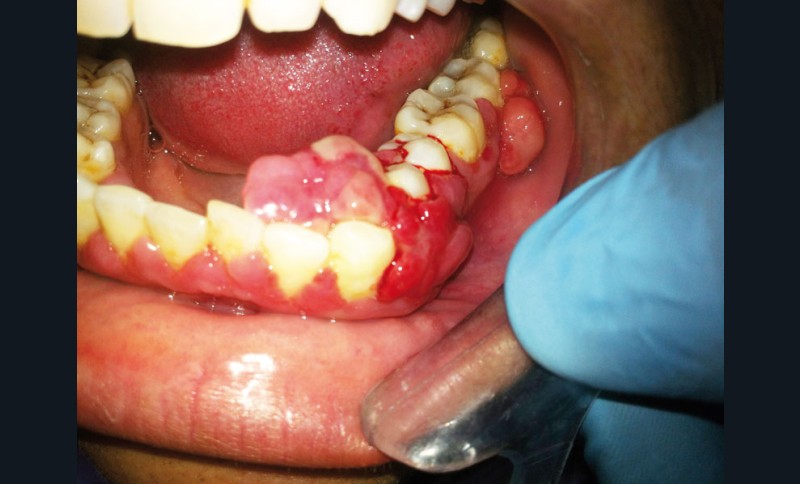

Elles s’identifient par une inflammation gingivale, caractérisée par une gencive rouge, voire violacée, œdématiée, qui saigne au brossage et/ou spontanément (fig. 1).

La spécificité des gingivites est l’absence de perte d’attache (ou de poches parodontales) et de destruction osseuse.

Ainsi, lors des périodes de désordres hormonaux, comme la puberté, la grossesse et la ménopause, on observe fréquemment des inflammations exacerbées qui peuvent révéler une susceptibilité de l’hôte aux maladies parodontales. (fig. 2 et 3).